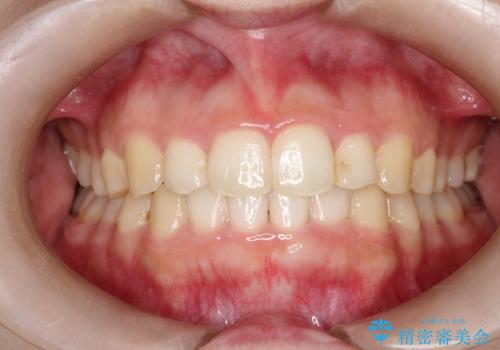

インビザラインでの前歯のガタガタの矯正

- 1年1ヶ月

使用時間を守っていただけたので、スムーズに矯正を終了することができました。